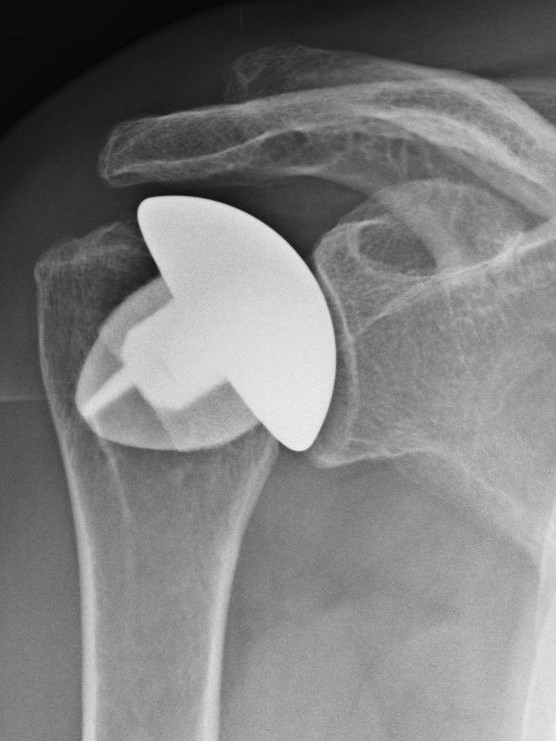

Schaftfreie Schulterendoprothese (Humeruskopfersatz)

Wann immer möglich wird ein sog. Humeruskopfersatz verwendet. Diese schaftfreie Schulterendoprothese erlaubt einen sehr knochensparenden Ersatz des Schultergelenkes und ermöglicht auch einen Austausch der Gelenkpfanne, falls diese sich im Laufe der Jahre auch abnutzt. Vorraussetzung für den alleinigen Ersatz der Kopfes ist eine ausreichend gute Knorpelschicht auf der Pfanne. Sollte irgendwann einmal eine Wechseloperation notwendig sein, bleiben durch die knochensparende Implantation alle Möglichkeiten für einen Wechsel der Prothese erhalten. Das Fallbeispiel zeigt eine Nekrose (Abgestorbener Knochen) eines großen Teils des Oberarmkopfes. Das Bild mit eingebrachter Kopf-Prothese den Zustand 5 Jahre nach der Operation.